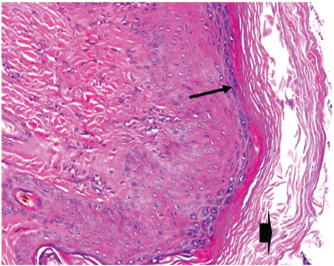

At 7 days post wounding; the inflammatory reaction was moderate and characterized by polymorphonuclear cells and macrophages infiltration with the presence of small scab covering the wound surface. Early evidence of epithelization was detected and represented by the proliferation of epidermal epithelium under the scab. There was marked thickening and hyperplastic proliferation of epidermal epithelium at the free wound edge (Fig. 6). The dermal tissue underlying the wound area showed few polymorphonuclear cells infiltration and more abundant mononuclear cells. Fibroplasia and angiogenesis were detected in the dermis and more extensive in deeper areas of the dermis which characterized by fibroblast and angioblast proliferation forming immature young granulation tissue (Fig. 7). At 14 days post wounding, the wound area was covered by a complete layer of epidermal epithelium indicating a good epithelization rate of the wound. Proliferation of cutaneous appendages was detected. The newly formed epithelium was thick and showed partial keratinization and epithelial differentiated stratum containing polyhedral keratinocyte with the appearance of keratohyalin granules in their cytoplasm (Fig. 8). The dermal tissue showed deposition of parallel well organized and interconnected collagen bundles that arranged parallel to epidermis associated with enhanced angiogenesis represented by well-developed blood capillaries (Fig. 9). At 21 days post wounding, remodeling of the formed epithelium with relatively small scar formation and mild restoration of skin appendages. Keratinized and differentiated stratum comprising the covering epithelium and the newly formed skin appendages from the basal epidermal epithelium were detected (Fig. 10). The dermal tissue revealed well-formed organized tissue consisted of parallel compact and interconnected bundles of collagen with scant angiogenesis (Fig. 11). At 28 days post wounding, well-formed scar tissue covering highly cellular organized tissue was detected (Fig. 12). The dermal tissue revealed well-arranged compact collagen bundles containing scarce blood vessels (Fig. 13).

Fig. 10. Skin of a goat from electroacupuncture group at 21 days post wounding showing keratinized (arrow head) and differentiated stratum comprising the covering epithelium (*) and the newly formed skin appendages from the basal epidermal epithelium (HE ×200).

Fig. 12. Skin of a goat from electroacupuncture group at 28 days post wounding showing well-formed scar tissue (arrow head) covering highly cellular organized tissue (HE ×100).

Fig. 13. Skin of a goat from electroacupuncture group at 28 days post wounding showing well arranged compact collagen bundles (arrow head) containing scarce blood vessels (HE ×200).